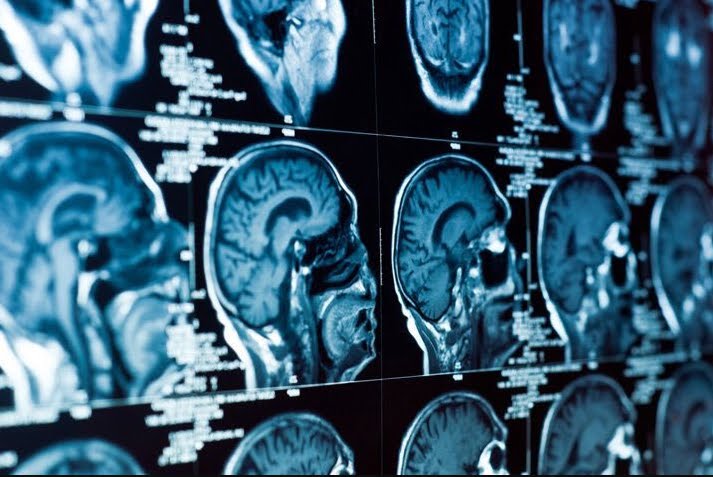

Attualmente, l’unico metodo affidabile per la diagnosi è la tomografia computerizzata (TC o TAC): un esame disponibile solo in alcuni nosocomi e che, oltre ad essere costoso, richiede molto tempo ed espone a radiazioni. Subendo un colpo alla testa, alcune cellule cerebrali vengono danneggiate e rilasciano tra l’altro delle proteine chiamate H-FABP, facendone aumentare il loro tasso nel sangue.